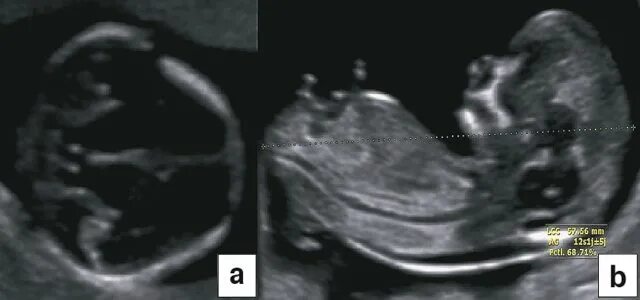

Узи аномалий